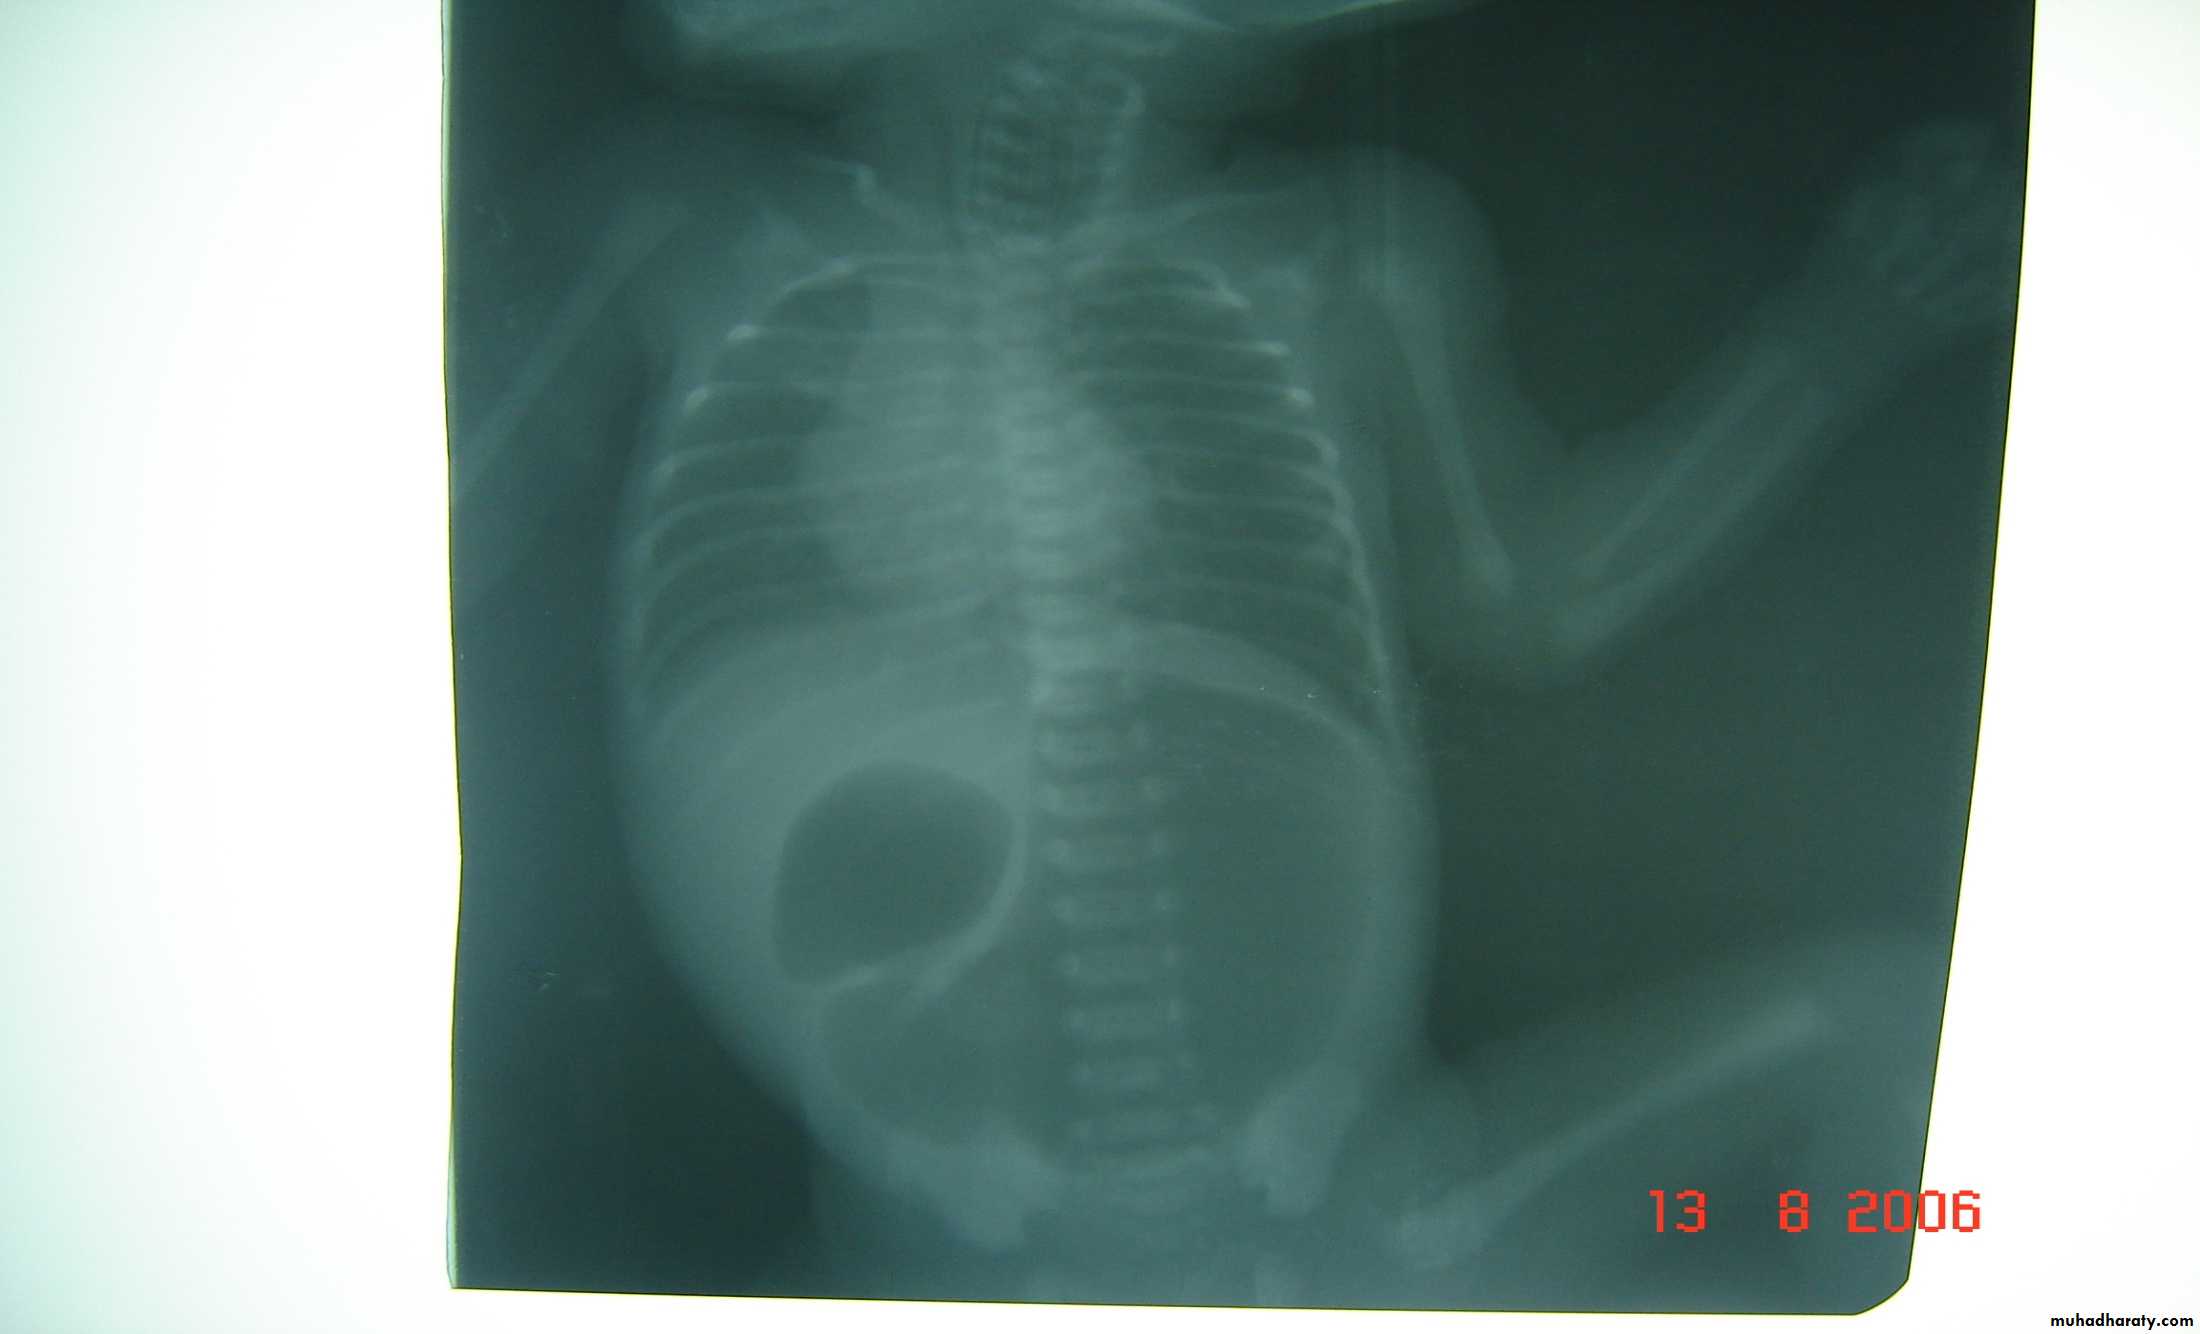

Bowel Obstruction

first photo upper bowel obstruction // second photo lower bowel obstructionDescription:

double bubble signCauses of obstruction in the first photo:

1- duodenal obstruction2- duodenal atresia

3- annular pancreas

4- mal-rotaion of bowel

Cardinal symptoms of bowel obstruction (first photo):

1- mild abdominal distention (epigastric distention)2- failure if pass of meconium

3- bile stain vomiting

In pediatric we cannot say small or large bowel obstruction but we say upper

or lower bowel obstruction